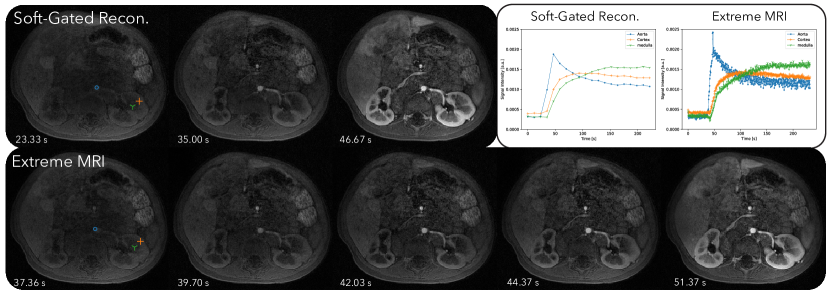

4.1.3 Third DCE dataset

Figure 8 and Supporting Information Video S9 and S10 compare the proposed method with the soft-gated reconstruction. From Supporting Information Video S9, regular breathing motion can be seen in the proposed reconstruction. Contrast dynamics starting from the aorta, and slowly filling in the cortex and the medulla can be observed. The aortic temporal changes can be seen at a higher frame-rate for the proposed reconstruction than for the soft-gated reconstruction.

Figure 4, 6, and 8 all show that the proposed reconstruction displays much finer dynamics that are not represented in soft-gated reconstructions with low frame-rates. Distinct phases of contrast enhancements in different organs can be seen, which are more physiologically accurate. The benefits of higher temporal resolution can also be seen from signal intensity curves. In particular, signal intensity peaks of the aorta are much higher in the proposed reconstruction, but are averaged out in the soft-gated reconstruction. While bulk motion still affects the overall image quality as shown in Figure 6, the proposed reconstruction allows us to retrospectively adjust for bulk motion when computing the signal intensity curves, which can be useful for quantification purposes.